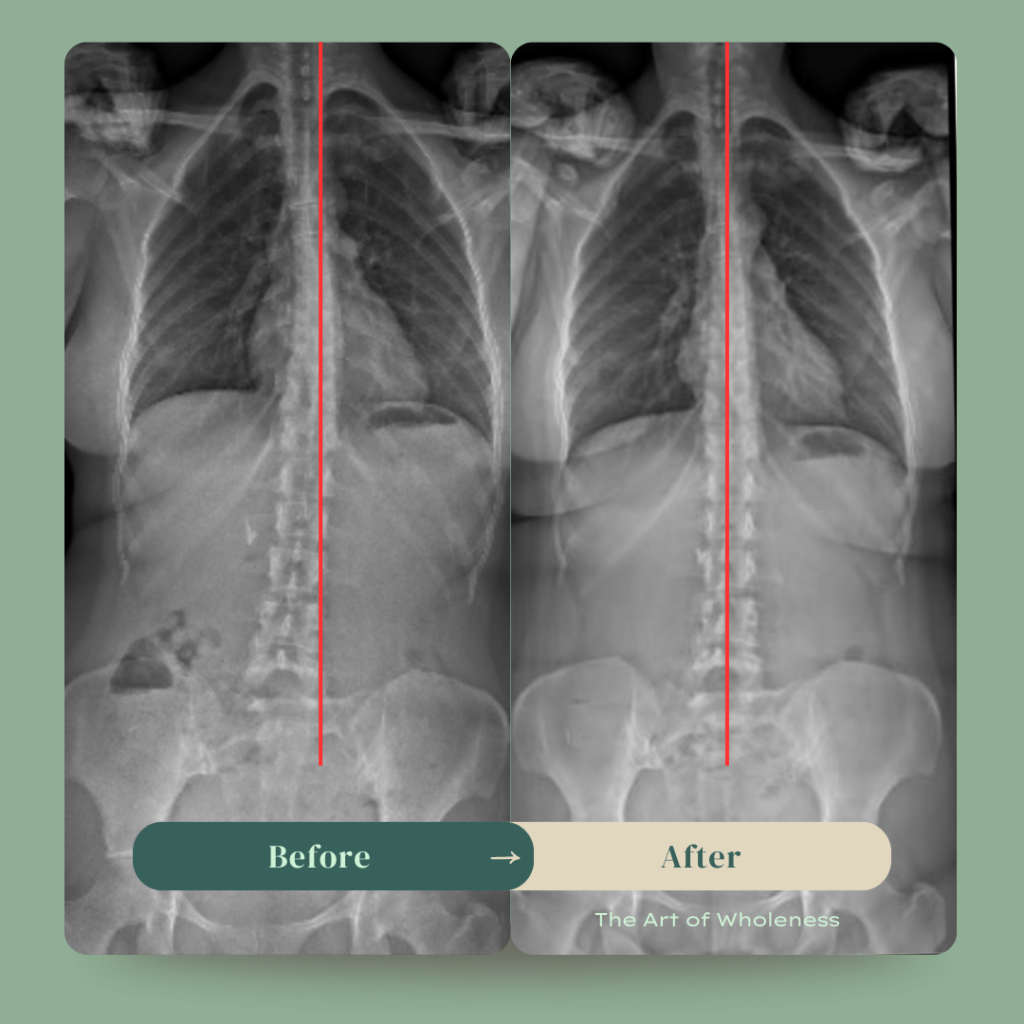

Around this same time, both my daughter and myself began to receive BodyTalk sessions with my now mentor Neil. Together Neil and I slowly unveiled and released many layers of my own trauma, began healing generations of epigenetic trauma and even managed to straighten the scoliosis in my spine (after being told it was impossible to do so by specialists), all through this gentle, non-invasive healing modality. Over time, both myself and my daughter experienced incredible healing.